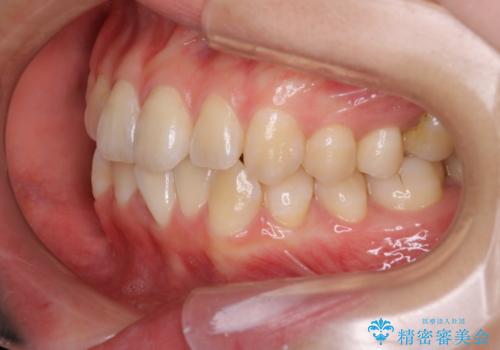

- 患者様は、右下第2小臼歯(5番)の先天欠如により乳歯が残存している状態でした。

加えて、**下顎前歯部に叢生(歯のがたつき)**が見られ、審美的・機能的な改善を希望されて来院されました。

診査の結果、乳歯は長期間機能していましたが、将来的な脱落のリスクが高く、インプラントによる永久歯の補綴が望ましいと判断しました。

また、欠損部にインプラントを埋入するには、前後の歯の傾斜改善とスペース確保のための矯正治療が必要でした。

下顎前歯の叢生も同時に改善できるよう、全体的なワイヤー矯正による治療計画を立案しました。